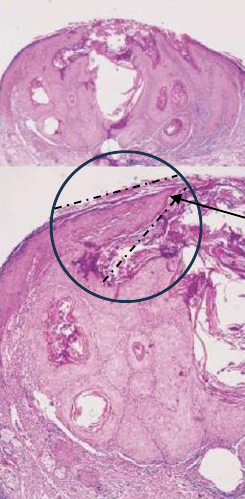

TNM staging

- Tumor: 原發性腫瘤(primary tumor)的大小和侵犯範圍

- 大小(cm)

- 深度 (DOI,mm)

TX: 無法評估Tis: carcinoma in situ

OSCC and HPV- OPSCC staging

- T

| DOI(mm) \ size(cm) | < 2 | 2~4 | > 4 |

|---|---|---|---|

| < 5 | T1 | T2 | T3 |

| 5~10 | T2 | T2 | T3 |

| >10 | ? | T3 | T3 |